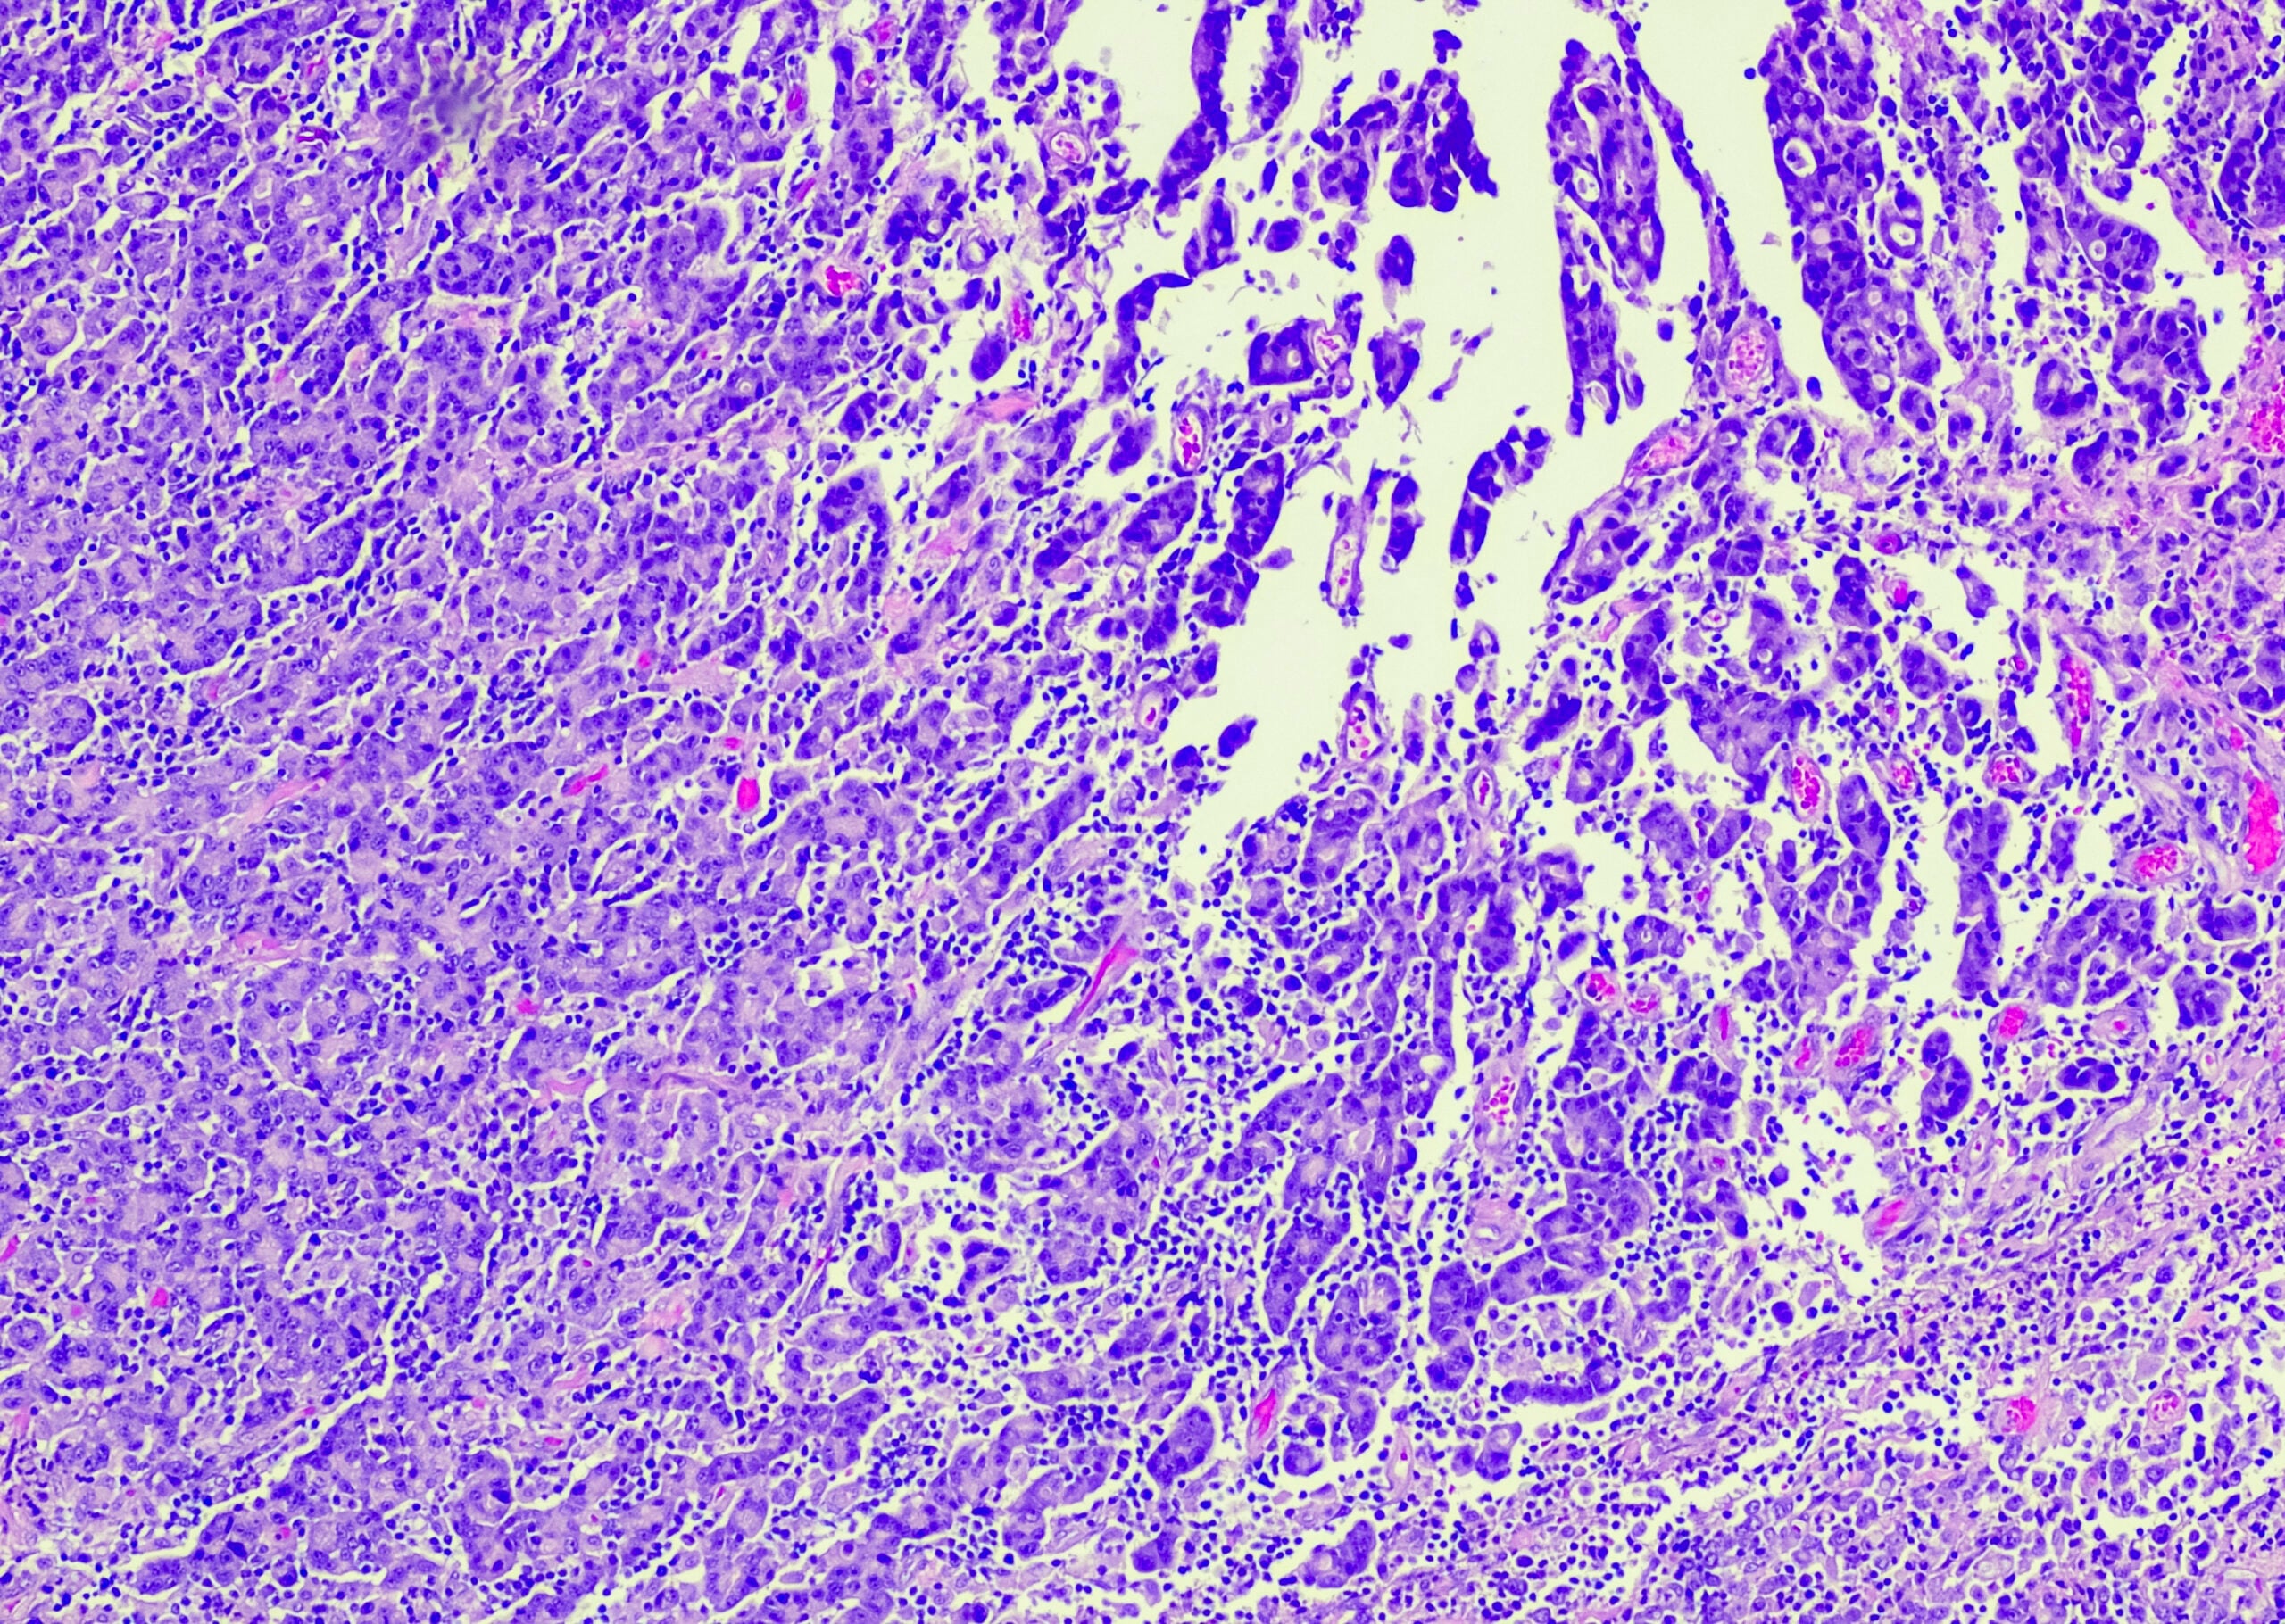

Multilocular cystic renal cell carcinoma (MCRCC)